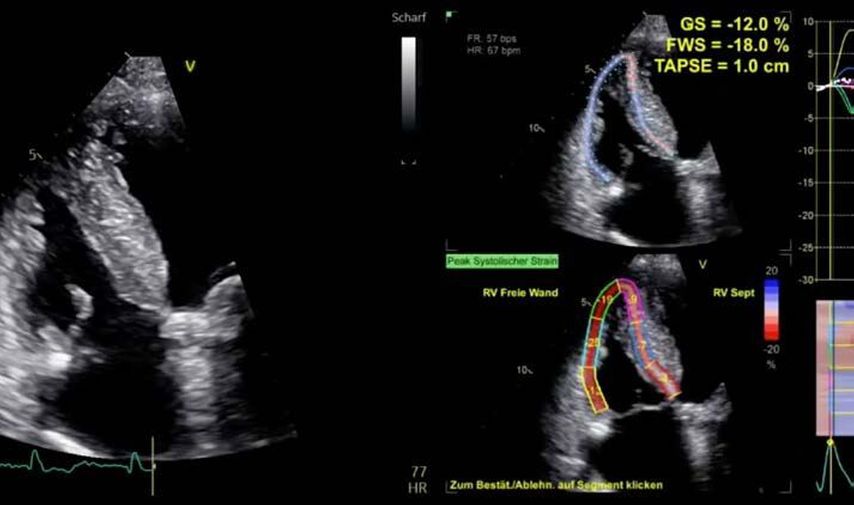

Im Echolabor des Pyhrn-Eisenwurzen Klinikums Steyr wird jede Form der Myokardwandverdickung mittels einer vollständigen Standardechokardiografie untersucht.2 Dabei wird auch ein Fokus auf die kontrastmittelunterstützte Sonografie gelegt, um die tatsächliche Dicke des Myokards zu vermessen.3 Die Verdickung sollte optimalerweise mittels 3D-LV-Massenmessung erfolgen. Die Messung im 2D-Bild ist dahingehend unterlegen. Ebenso wird jede Myokardwandverdickung mittels 2D-„strain imaging“ in der transthorakalen Echokardiografie (TTE) untersucht.4–6 Der „strain“ ist eine Messung der longitudinalen Funktion des Herzens (Video 1).

Bei der hypertrophen CMP gibt es die Besonderheit, dass versucht werden muss, einen Ausflusstraktgradienten (LVOTO) zu messen, da dieser für die Prognose und Therapie relevant ist.1 Eine neue Therapie der hypertrophen obstruktiven CMP (HOCMP) sind kardiale Myosininhibitoren. Diese können zu einem „reverse remodeling“ des Herzens führen und Parameter, wie den „strain“, neben der Reduktion des Ausflusstraktgradienten unter Therapie deutlich verbessern.1,8,9

1. Fall: HCMP vs. HOCMP, männlich 52a

Der erste Fall beschäftigt sich mit einem Patienten mit einer hypertrophen Kardiomyopathie (HCMP). Er gibt eine deutliche Belastungsdyspnoe sowie einen ausgeprägten Leistungsknick an. Es wurde infolgedessen eine Untersuchung mittels standardisierter Echokardiografie inklusive „strain imaging“ durchgeführt. Der globale longitudinale „strain“ (GLS) mit –16% in Ruhe war gering reduziert. Es konnte kein relevanter LVOT-Gradient in Ruhe nachgewiesen werden. In der Belastungssituation (Handgrip, Valsalva, Kniebeugen und als Vorbereitung zur Untersuchung ein ausgiebiges Frühstück und Kaffee sowie ein am Vorabend konsumiertes Bier) konnte bei Kniebeugen mit einer Herzfrequenz von 126/min ein Spitzengradient bis 52mmHg dargestellt werden. Somit ergibt sich die Diagnose einer HOCMP mit einem belastungsinduzierten Gradienten. Bei bereits bestehender und ausgereizter Therapie unter Betablocker besteht die Indikation zur Therapie mittels des kardialen Myosininhibitors Mavacamten (Klasse-IIa-Empfehlung laut ESC).1 Darunter verbesserte sich die klinische Situation des Patienten deutlich, der Patient konnte uneingeschränkt Sport ausüben. Über die Zeit kam es zu einer geringen Reduktion der LV-Masse und einer geringen Zunahme des LV-„strain“. Die Belastungssituation zeigte durchwegs normale „strain“-Werte mit –20% (mit regionaler Reduktion bei Myokardwandverdickung im Sinne einer Hypertrophie). Die myokardiale Arbeit beim konkreten Patientenfall ist ebenso in Ruhe im grenzwertigen und unter Belastung im guten Normalbereich.6,8,9 Der Patient ist derzeit unter 5mg Mavacamten einmal täglich optimal eingestellt. Die EF in Ruhe ist konstant bei 50–55%. In Video 2 werden unterschiedliche Gradienten dargestellt, um eine HOCMP mit LVOTO von z.B. einer Mitralklappeninsuffizienz zu unterscheiden.Die Verdachtsdiagnose wurde mithilfe der Echokardiografie gestellt und durch das septal betonte „patchy“ LGE im MRT bestätigt.1,5